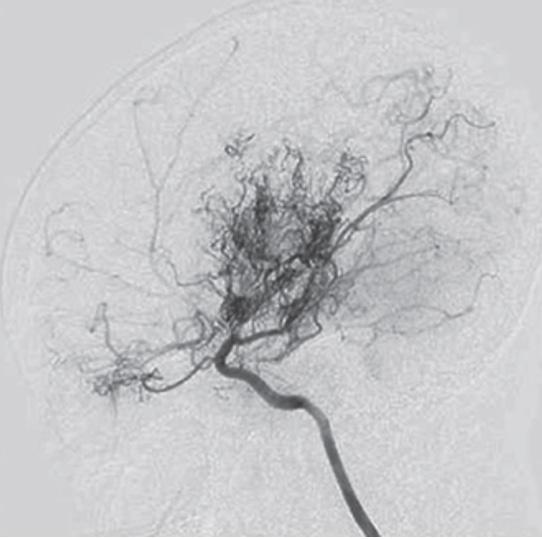

2. Angiografia nella malattia di Moyamoya; appare evidente un restringimento significativo della carotide interna e la presenza caratteristica dei collaterali “a nuvola di fumo” con perfusione corticale ridotta.

• Non infiammatorie. La dissezione arteriosa intracranica consegue spesso eventi traumatici ma può manifestarsi anche spontaneamente nei soggetti affetti da patologie del collagene (sindrome di Marfan, sindrome di Ehlers-Danlos ecc.). Altra condizione non infiammatoria è la malattia di Moyamoya (6-10% degli AIS), patologia cerebrovascolare occlusiva progressiva e idiopatica che coinvolge il tratto distale dell’arteria carotide interna e dei suoi rami. La stenosi progressiva del lume vascolare determina la creazione di una fitta rete di vasi collaterali alla base del cranio, che all’angiografia determinano l’immagine suggestiva “a nuvo-

la di fumo” [Figura 2]. È una condizione più frequente in giovani ragazze di etnia asiatica e nei soggetti affetti da sindrome di Down, neurofibromatosi di tipo 1 e anemia a cellule falciformi. Infine, la displasia fibromuscolare si caratterizza per displasia fibrosa e conseguente stenosi a carico dei vasi di medio calibro con possibile interessamento sia intra che extra-cerebrale.